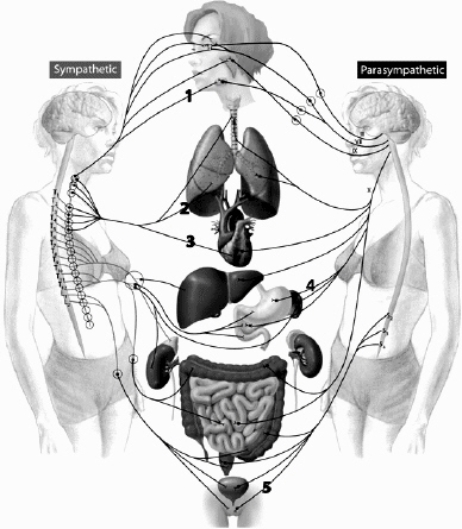

Use this figure to answer the following questions.

Identify the correct statement(s):

a. Neuron 5 causes contraction of its effector.

b. Neuron 6 is stimulated by ACh released from a preganglionic neuron.

c. Neuron 1 causes constriction of bronchioles

d. Neuron 2 releases a chemical that binds to nicotinic receptors on a postganglionic neuron.

e. Two of the above.